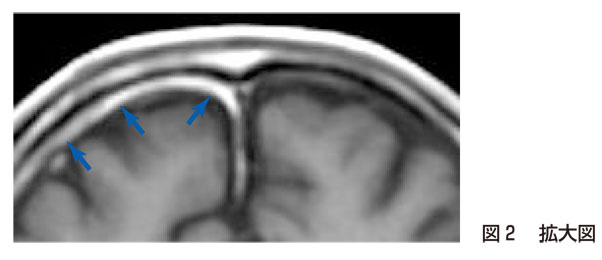

研修医:あっ! 右前頭葉前面に位置する線状の構造が,左より明らかに目立っています!(→)

研修医:はい.(造影T1強調画像である)図2を外側から順にみると,皮下組織(高信号)→外板(無信号)→板間層(高信号)→内板(無信号)→硬膜(一般には中等度の信号,本例では右側が肥厚し高信号:→)→くも膜下腔(著明な低信号)→灰白質となっているわけですね! つまり,この症例では右前頭部で硬膜の肥厚と造影効果が目立っているのですね(図2拡大図を参照).

指導医:その通り! 本症例では肺癌の既往があり,また,1年前のMRIでは硬膜肥厚が認められなかった点などから,硬膜転移と診断されたんだ.